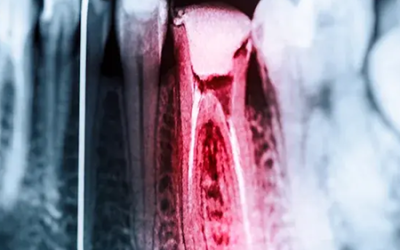

Endodonzia (cura canalare)